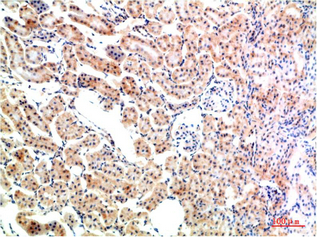

Applications :WB, IHC

| Recommended dilutions: | WB 1:500-2,000 IHC 1:50-300 |

| Specificity: | The antibody detects endogenous IkB α protein |